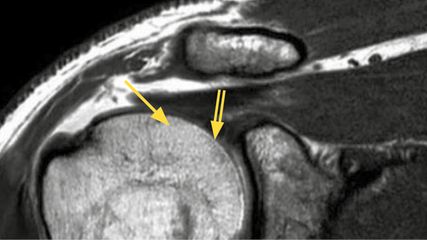

Magnetresonanztomografie (MRT): Das MRT, häufig auch als hochauflösende MRT-Arthrografie, spielt eine zentrale Rolle in der Diagnostik. Nach operativen Eingriffen kann die Aussagekraft jedoch durch Metallartefakte oder Narbengewebe eingeschränkt sein, was die Interpretation erschweren kann. Bei der Interpretation des MRTs muss berücksichtigt werden, dass sich die Rotatorenmanschette auch nach bis zu 12 Monaten noch in der Heilungsphase befinden kann. Areale mit Signalanstieg können einer Reruptur ähneln. Rerupturen sind am deutlichsten in den T2- und PD-gewichteten Schichten beurteilbar.25

Der Muskelstatus ist entscheidend für den Erfolg der Revisionschirurgie und wird durch die Goutallier-Klassifikation hinsichtlich der fettigen Infiltration beurteilt. Eine geringe Infiltration (Grad 0–1) ist vielversprechend für eine erfolgreiche Rekonstruktion, während eine höhere Infiltration (Grad 2–4) das Risiko für eine (Re)Reruptur und progrediente Muskeldegeneration erhöht. Goutallier et al. zeigten mit einer klinischen Folgestudie nach Index- Beschreibung der Klassifikation im CT 1994, dass präoperative Atrophien mit höheren Rerupturraten assoziiert sind, insbesondere im fortgeschrittenen Stadium. Besonders die fettige Infiltration wurde als wichtiger negativer Prognosefaktor identifiziert.38

In der Gruppe der Rerupturen konnte außerdem eine Progression der strukturellen Veränderungen – auch im angelagerten Muskel (ISP bei SSP-Reruptur) – gezeigt werden. Diese fettige Degeneration korreliert dabei signifikant mit dem klinischen Outcome.39 Die Klassifikation von Rotatorenmanschetten-Rerupturen erfolgt typischerweise nach Sugaya und unterscheidet fünf Typen (Tab. 1).40